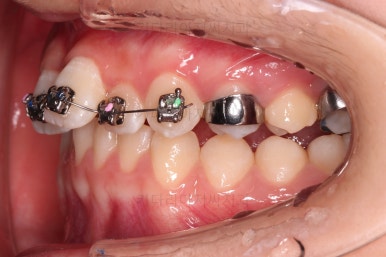

3. 치료경과

적절한 시기에 시차를 두고 순차적으로 브라켓을 부착합니다.

장치 부착 직후의 눈에 보이는 모습과 옆라인의 변화 확인해 주시고요.

이번 환자분은 장치를 부착했다고 해서 옆라인이 거의 차이가 나지 않는 케이스였습니다.

적절한 시기에 아랫니도 장치를 구성하고요.

과개교합 및 앵글씨 2급 부정교합 개선을 도와주는 장치도 보조적으로 활용해 주었습니다.

가지런한 느낌은 좋아졌고, 과개교합도 깔끔하게 개선이 되었습니다.

이제부터는 부정교합을 개선하면서 위아래 어금니 맞물림을 개선해 나갑니다.

성인이었다면 미니스크류 혹은 발치가 필요한 상황이었을 것이나 아직 청소년기이고 약간의 성장여력을 활용할 수 있는 상황이었으므로 미니스크류나 발치 없이 개선해 나가보기로 했습니다.

교합이 개선됨에 따라 자연스럽게 중앙선도 좋아지고 있는 부분이 눈에 띄고요.

부정교합이 정말 많이 좋아졌습니다.